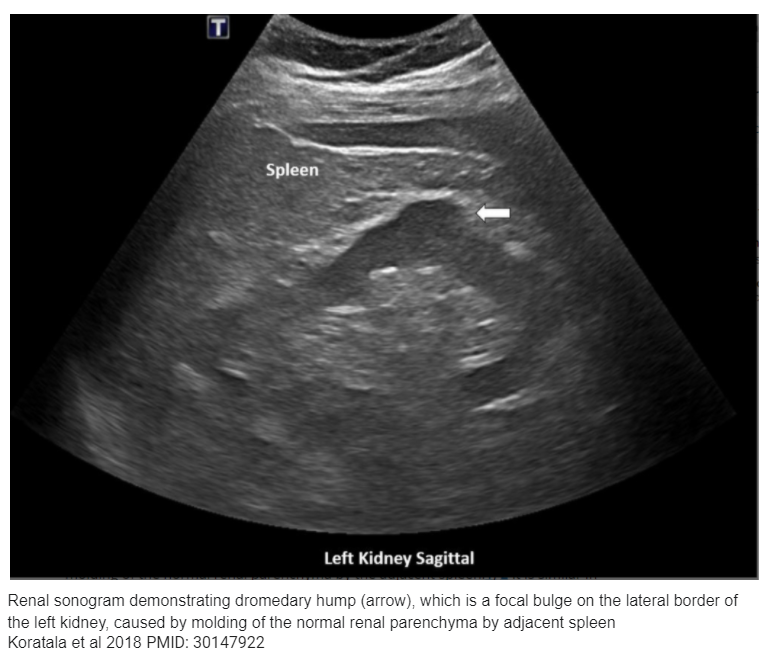

💥It is important to exclude pseudo mass/ tumor

💥Most common causes-

📌Congenital anomalies: Prominent renal columns of Bertin, dromedary humps